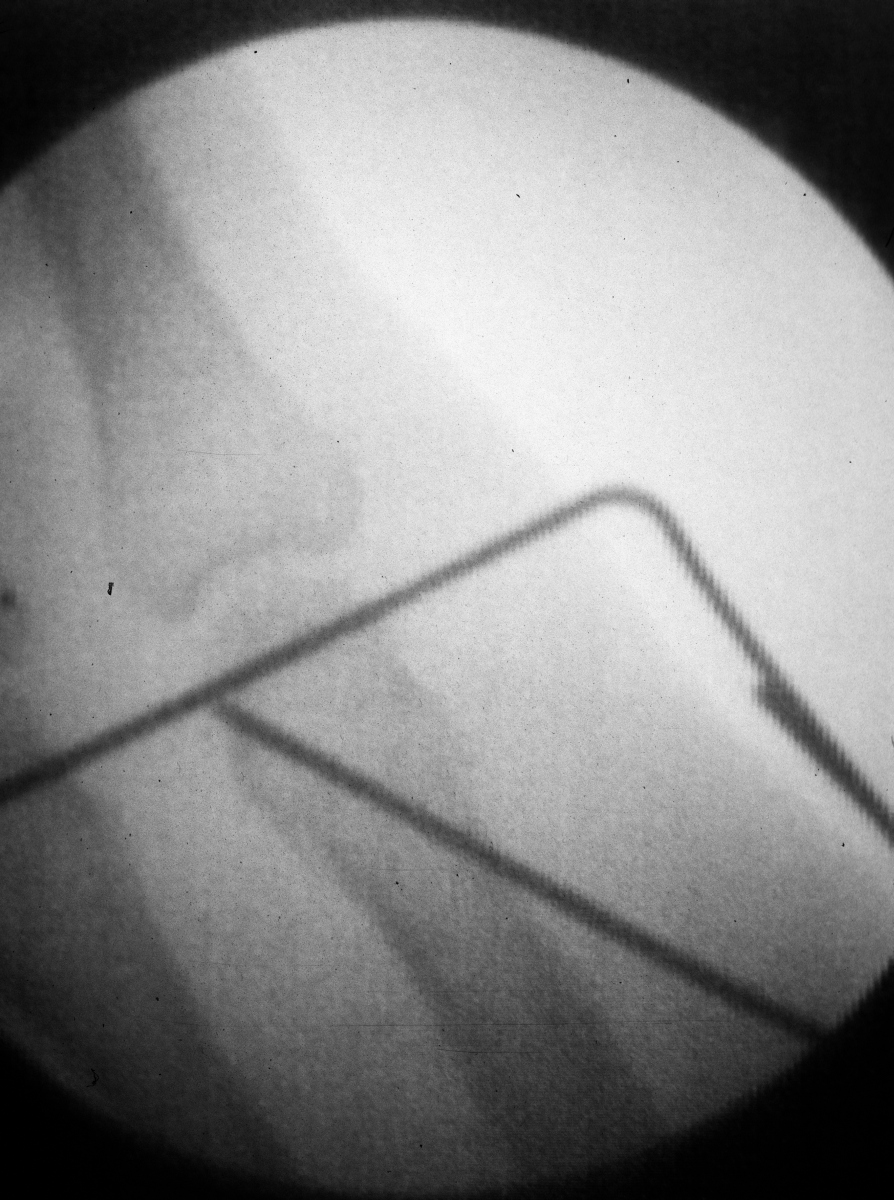

| Pins were left

protruding and bent to overlap. |

| Thermoplastic-pin

construct at 6 weeks, immediately prior to removal. |